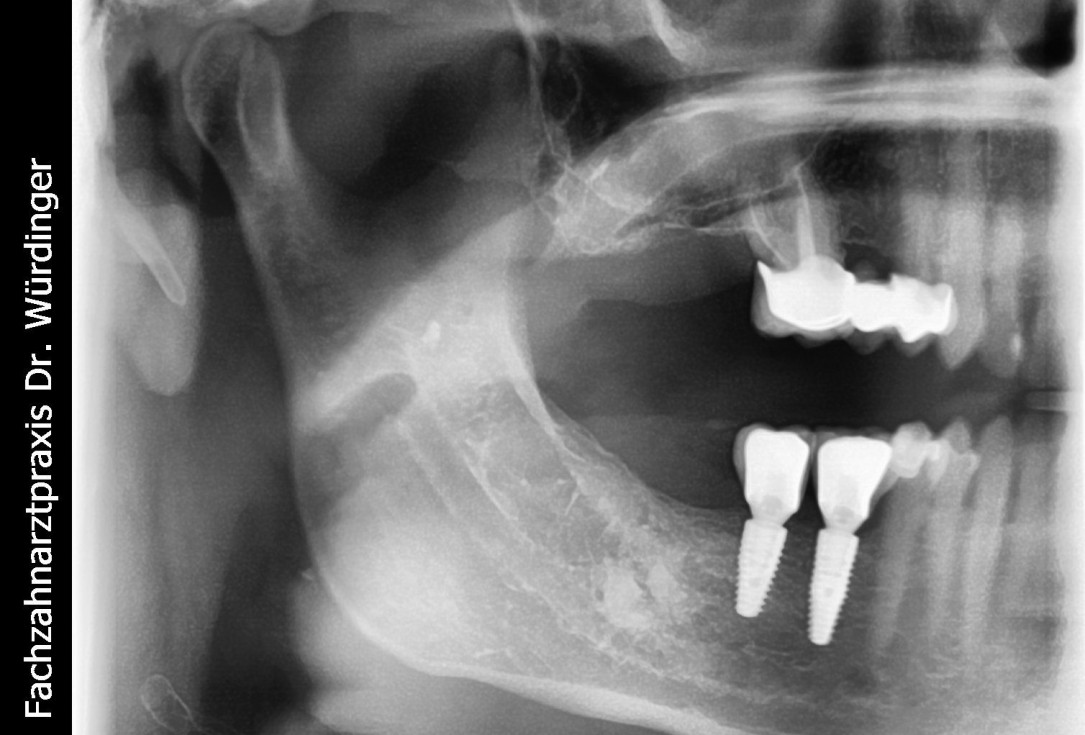

28/28 - Radiographic control of the final prosthesis - excellent stability of the augmented bone tissueThree-dimensional augmentation with maxgraft® cortico - Dr. R. Würdinger